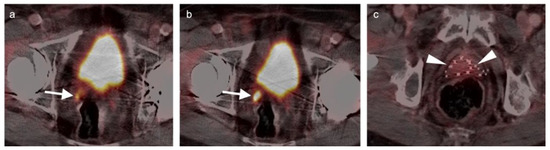

- Robertson, N.; Hricak, H.; Sonoda, Y.; Sosa, R.; Benz, M.; Lyons, G.; Abu-Rustum, N.; Sala, E.; Vargas, H. The impact of FDG-PET/CT in the management of patients with vulvar and vaginal cancer. Gynecol. Oncol. 2016, 140, 420–424. [Google Scholar] [CrossRef]

- Lamoreaux, W.T.; Grigsby, P.W.; Dehdashti, F.; Zoberi, I.; Powell, M.A.; Gibb, R.K.; Rader, J.S.; Mutch, D.G.; Siegel, B.A. FDG-PET evaluation of vaginal carcinoma. Int. J. Radiat. Oncol. 2005, 62, 733–737. [Google Scholar] [CrossRef]

- Kilcoyne, A.; Gottumukkala, R.V.; Kang, S.K.; Akin, E.A.; Hauck, C.; Hindman, N.M.; Huang, C.; Khanna, N.; Paspulati, R.; Rauch, G.M.; et al. ACR Appropriateness Criteria® Staging and Follow-up of Primary Vaginal Cancer. J. Am. Coll. Radiol. 2021, 18, S442–S455. [Google Scholar] [CrossRef]